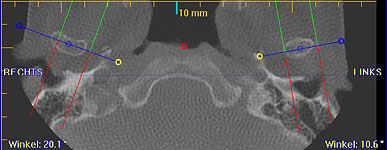

Im folgendem sehen Sie die Darstellung eines Teils des menschlichen Schädels mit Lokalisation des Nervkanales.

Frontalansicht |